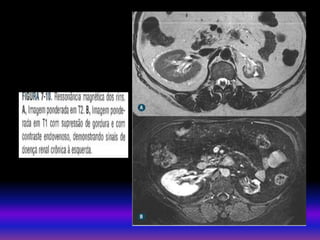

• RNM

Secuencias convencionais T1 e T2 permitem a detecção

de anormalidades estruturais e vasculares.

Util a RNM com gadolínio para pacientes alergicos aos

contrastes iodados.

Há risco de fibrose nefrogênica sistemica pelo gadolínio

(regras):

Ter creatinina dos pacientes maiores de 60 anos.

TFG entre 60 – 30 ml risco/benefício

TFG menor 30 ml Não usar.

• RNM Secuencias convencionaisT1 e T2 permitem a detecção de anormalidades estruturais e vasculares. Util a RNM com gadolínio para pacientes alergicos aos contrastes iodados. Há risco de fibrose nefrogênica sistemica pelo gadolínio (regras): Ter creatinina dos pacientes maiores de 60 anos. TFG entre 60 – 30 ml risco/benefício TFG menor 30 ml Não usar. MÉTODOS DE IMAGEM